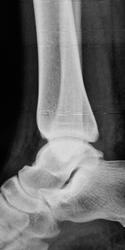

Травма. Пациент направлен на рентгенографию голеностопного сустава

Фрагментарный перелом наружной лодыжки, и ,кажеться, есть отрыв заднего бугорка таранной кости.

Классный перелом-филигранная работа, только верхушечка!

Отрывной перелом нижнего полюса наружной лодыжки. 3 недели в U-лонгете. Затем, даже если не срастается, то уже не болит, можно ходить далее. Перипроцесса не вижу, да и не знаю оного)